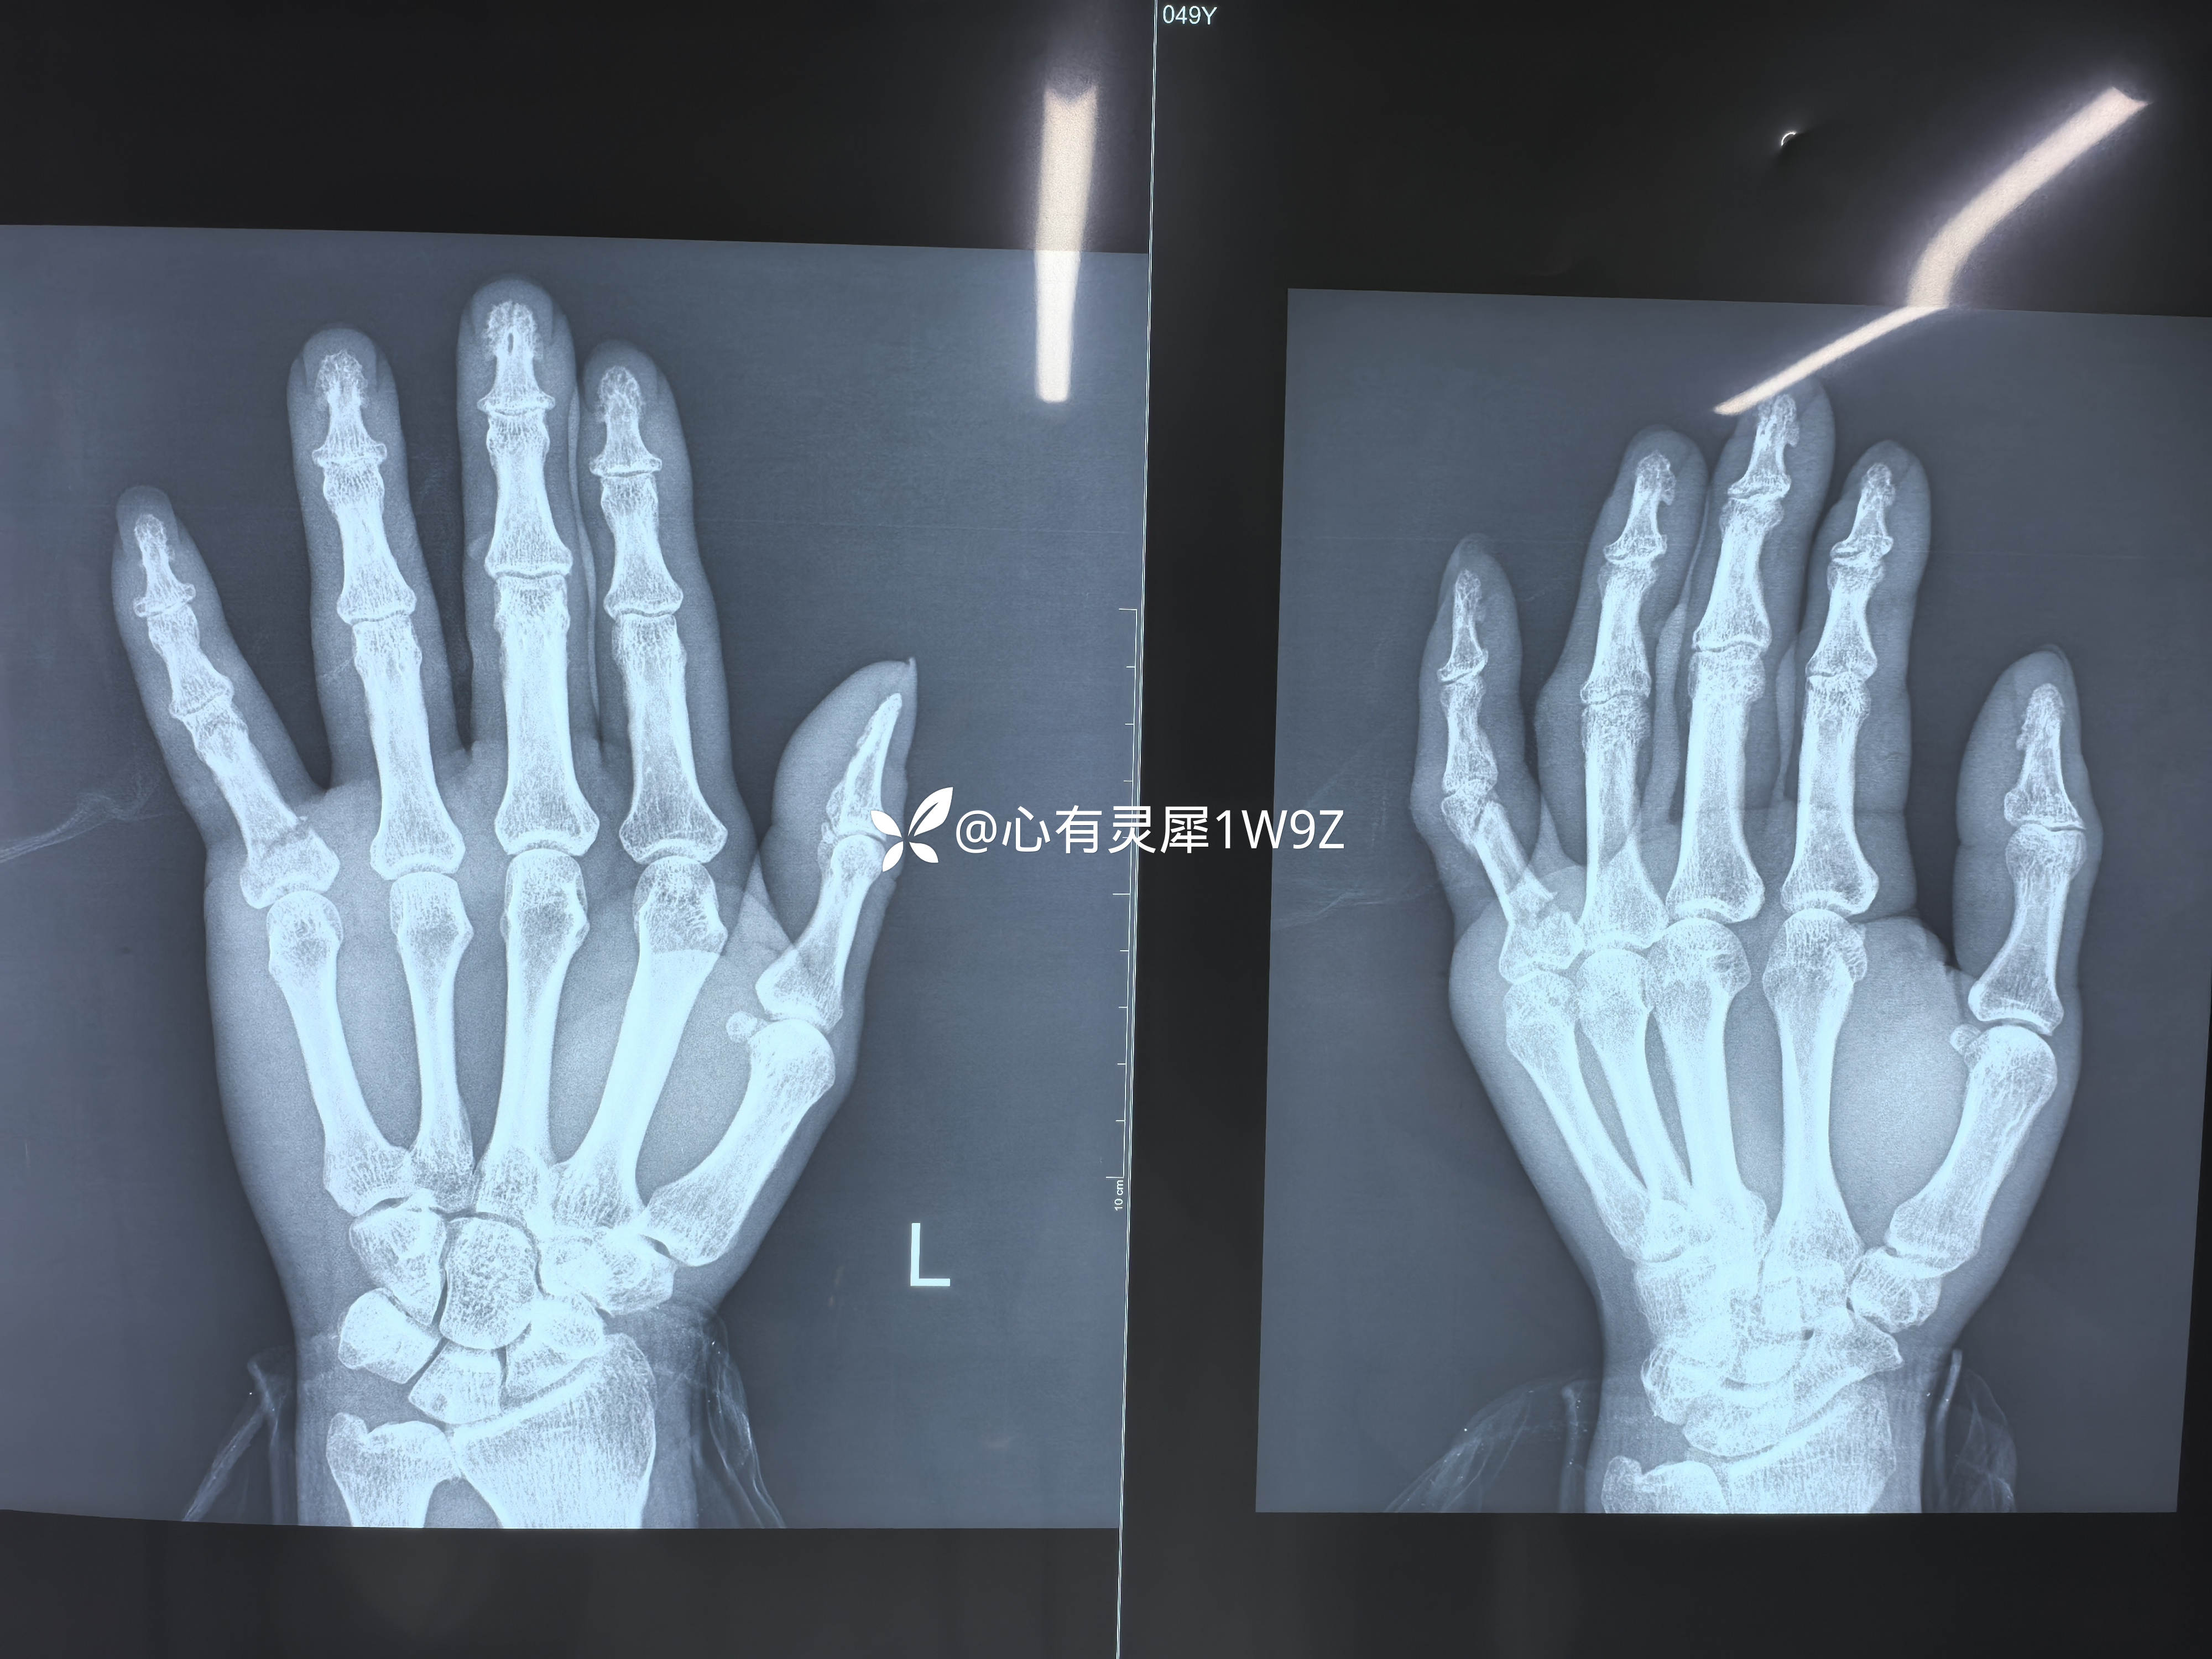

小指近节指骨两处骨折

【临床诊断】:左手小指近节指骨骨折